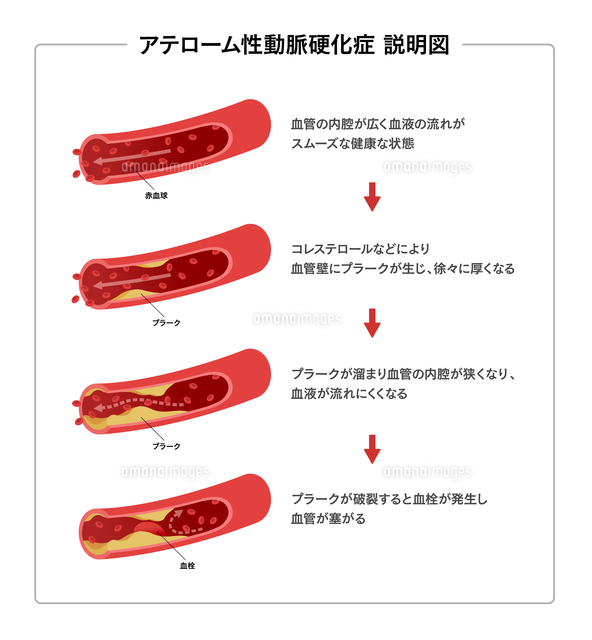

アテローム血栓性脳梗塞のイラスト イラスト素材6874946- フォトライブラリ。

血栓症 – Welcome to 佐野内科ハートクリニック。

動脈硬化、血栓形成。ベクトル医療イラスト。内部の臓器、血栓症、血管内皮のイラスト素材・ベクター Image 61855962。